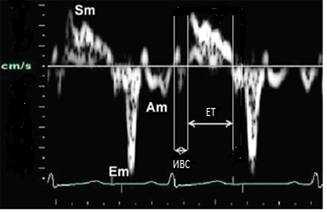

Анализ продольного движения миокарда проводился в верхушечном 4-камерном срезе сердца с синхронной записью мониторного отведения ЭКГ при задержке дыхания пациента в течение 5-10 сердечных циклов (рис. 1). Контрольный объем (5x8 мм) ТД размещался в латеральной и медиальной частях фиброзного кольца митрального клапана (МФК). Точкой начала отсчета временных фаз считали зубец R ЭКГ. Проводился анализ параметров ТД от латеральной (МФКл) и медиальной (МФКм) частей фиброзного кольца митрального клапана: ТМРИ вычислялся по ТД в медиальной и латеральной частях МФК по графикам максимальной скорости движения МФК как отношение разницы временного интервала между началом положительной волны ИВС до начала «Еm» (a’) и временем систолической волны Sm (b’), по формуле:

Рис. 1. Принцип расчета ТМРИ по ТД фиброзного кольца митрального клапана.

Материалы и методы: в проспективное исследование было включено 45 пациентов в возрасте от 45 до 65 лет с ИКМП, которые проходили лечение в кардиологическом отделении ГБУЗ АО «Городская клиническая больница № 4 имени В. И. Ленина» в 2013-2014 гг. Диагноз ИКМП выставлялись на основании жалоб, анамнеза заболевания, физикального обследования, инструментальных (ЭКГ, ЭХО-КГ, ХМЭКГ, коронарографии и др.) и лабораторных данных, согласно Рекомендаций по диагностике и лечению стабильной стенокардии ВНОК, 2008г., Рекомендаций по диагностике и ведению больных стабильной ИБС Американского кардиологического колледжа (АСС) и Американской ассоциации сердца (АНА) 2012 г., Рекомендаций по ведению стабильной коронарной болезни сердца Европейского общества кардиологов, 2013г.; Клинических рекомендаций по диагностике и лечению хронической ишемической болезни сердца МЗРФ 2013 г. и формулировали по Международной Классификации Болезней (X пересмотра). Для оценки тяжести хронической сердечной недостаточности (ХСН) использовали классификацию Нью-Йоркской ассоциации кардиологов (NewYorkHeartAssociation - NYHA) и классификацию Василенко и Стражеско. Критериями включения в исследование были: 1) наличие симптомов ХСН в покое и/или при физической нагрузке в течение последних 6 месяцев до исследования, 2) наличие ИБС и перенесенный в прошлом (за 6 месяцев и ранее) инфаркт миокарда (по анамнестическим данным и данным инструментальных исследований), 3) наличие систолической дисфункции миокарда левого желудочка (ФВ ЛЖ по Симпсону менее 45 %) 4) дилатация левого желудочка (индекс КДО > 110 мл/м2, индекс КСО > 80 мл/м2). Группу контроля составили 30 соматически здоровых лиц Астраханской области. Трансторакальная включала наряду с общепринятыми методиками (одномерной, двухмерной ЭхоКГ, импульсно-волновой и цветовой Д-ЭхоКГ) и импульсно-волновую ТДЭхоКГ на уровне МФК с последующей обработкой данных. Анализ продольного движения миокарда проводился в стандартном верхушечном, контрольный объем ТД (5×8 мм) размещали в латеральной и медиальной частях МФК в апикальном 4-камерном срезе в наиболее яркой цветовой зоне фиброзного кольца. Проводился анализ скоростных и временных параметров ТДЭхоКГ (Smmax-максимальная систолическая скорость миокарда ЛЖ, ИВСм - период изоволюмического сокращения МФК (мс), ЕТ сист - время выброса в систолу (мс)) полученных от латеральной (МФКл) и медиальной (МФКм) частей фиброзного кольцамитрального клапана (рис. 1).

Рис. 1. Принцип определения скоростных и временных показателей движения в систолу фиброзного кольца митрального клапана по ТДЭхоКГ